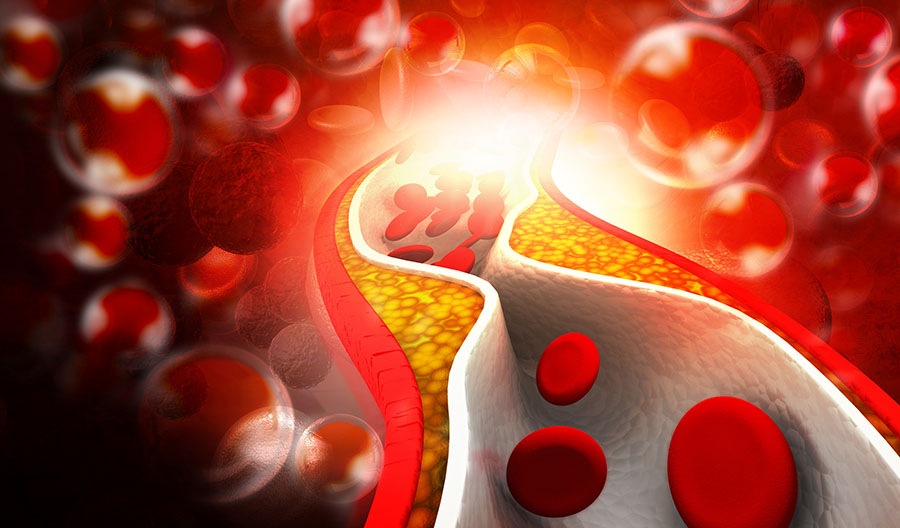

Холестерин в организме: влияние и функции (схемы и диаграммы)